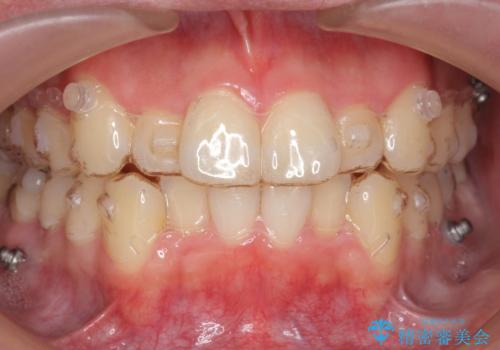

前歯のがたつき マウスピース矯正で 非抜歯で奥歯を後ろに下げる治療

- 前歯のがたつきを主訴に来院。

歯を抜かずに、奥歯を後ろに下げ、歯の両側をわずかに削って並べました。

奥歯を後ろに下げるのに、上下左右に矯正用ミニスクリューを入れています。

そのまま並べると戻りやすいのと、口元が出てしまうためです。

歯のがたつきがなくなると、歯ブラシがしやすくなり、茶色いステインも付きにくくなります。